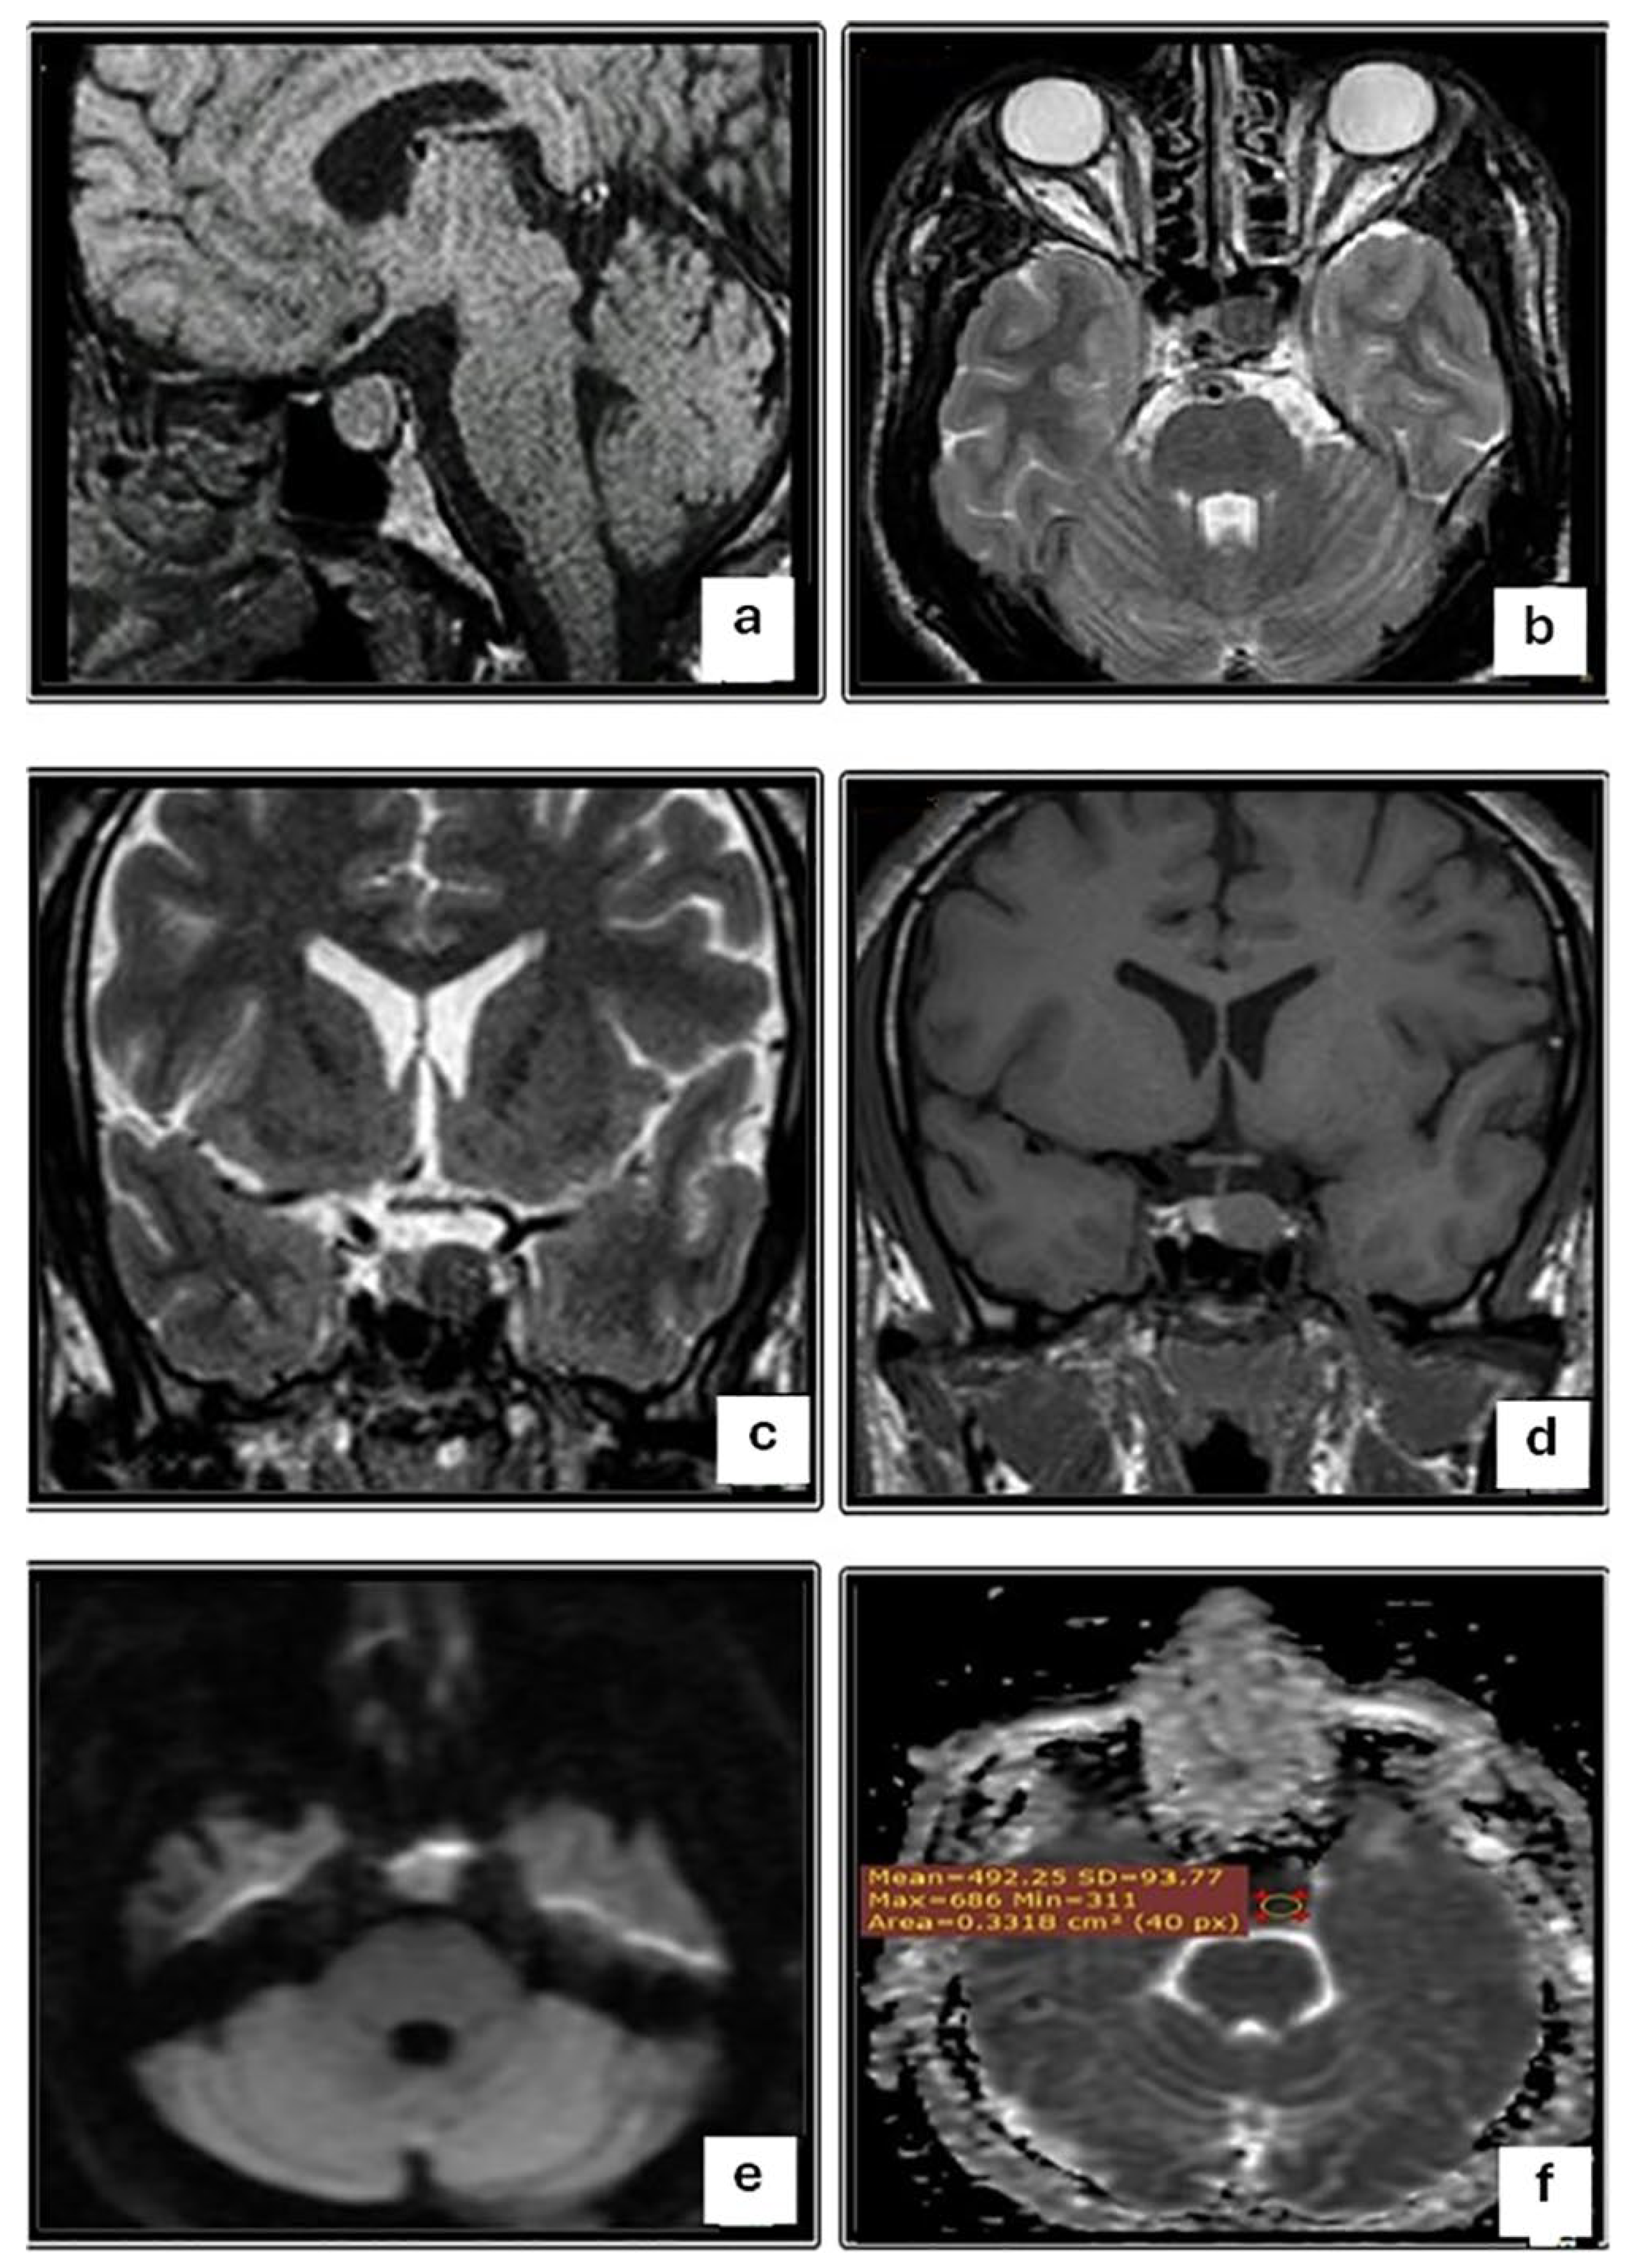

| Macroadenoma | p-Value | |||

|---|---|---|---|---|

| Total (n = 45) | Aspirable (n = 27) | Non-Aspirable (n = 18) | ||

| DWI (b 100) | <0.001 | |||

| Iso-intense | 9 (20.0) | 9 (33.3) | 0 (0) | |

| Hypo-intense | 15 (33.3) | 0 (0) | 15 (83.3) | |

| Hyper-intense | 21 (46.7) | 18 (66.7) | 3 (16.7) | |

| ADC map | 0.004 | |||

| Hypo-intense | 21 (46.7) | 18 (66.7) | 3 (16.7) | |

| Hyper-intense | 15 (33.3) | 0 (0) | 15 (83.3) | |

| ADC value, Mean ±SD (range) | 0.72 ± 0.25 (0.40–1.10) | 0.54 ± 0.19 (0.42–0.90) | 0.95 ± 0.08 (0.90–1.10) | 0.008 |